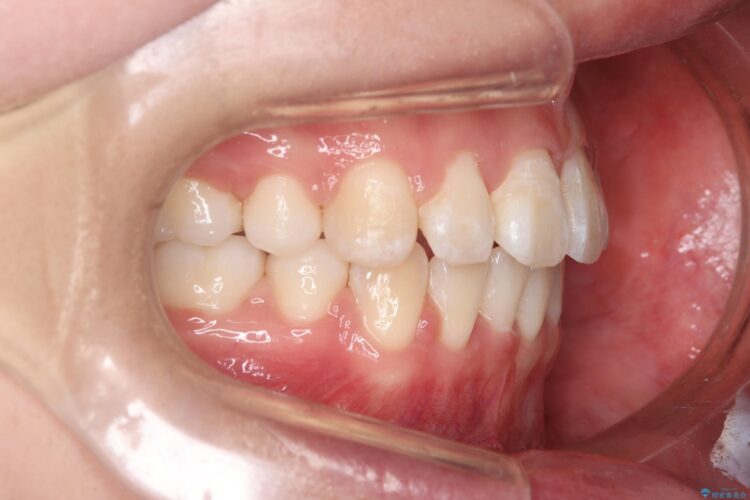

前歯のガつきと口元が出ていることを気にされご来院された患者様です。

上下4番目の歯を抜歯してガタつきを改善しながら口元を下げる治療計画を立てました。

抜歯矯正で口元を下げたことで、Eラインが大変綺麗になりました。

期間も1年9ヶ月と比較的短期間で治療完了することができました。